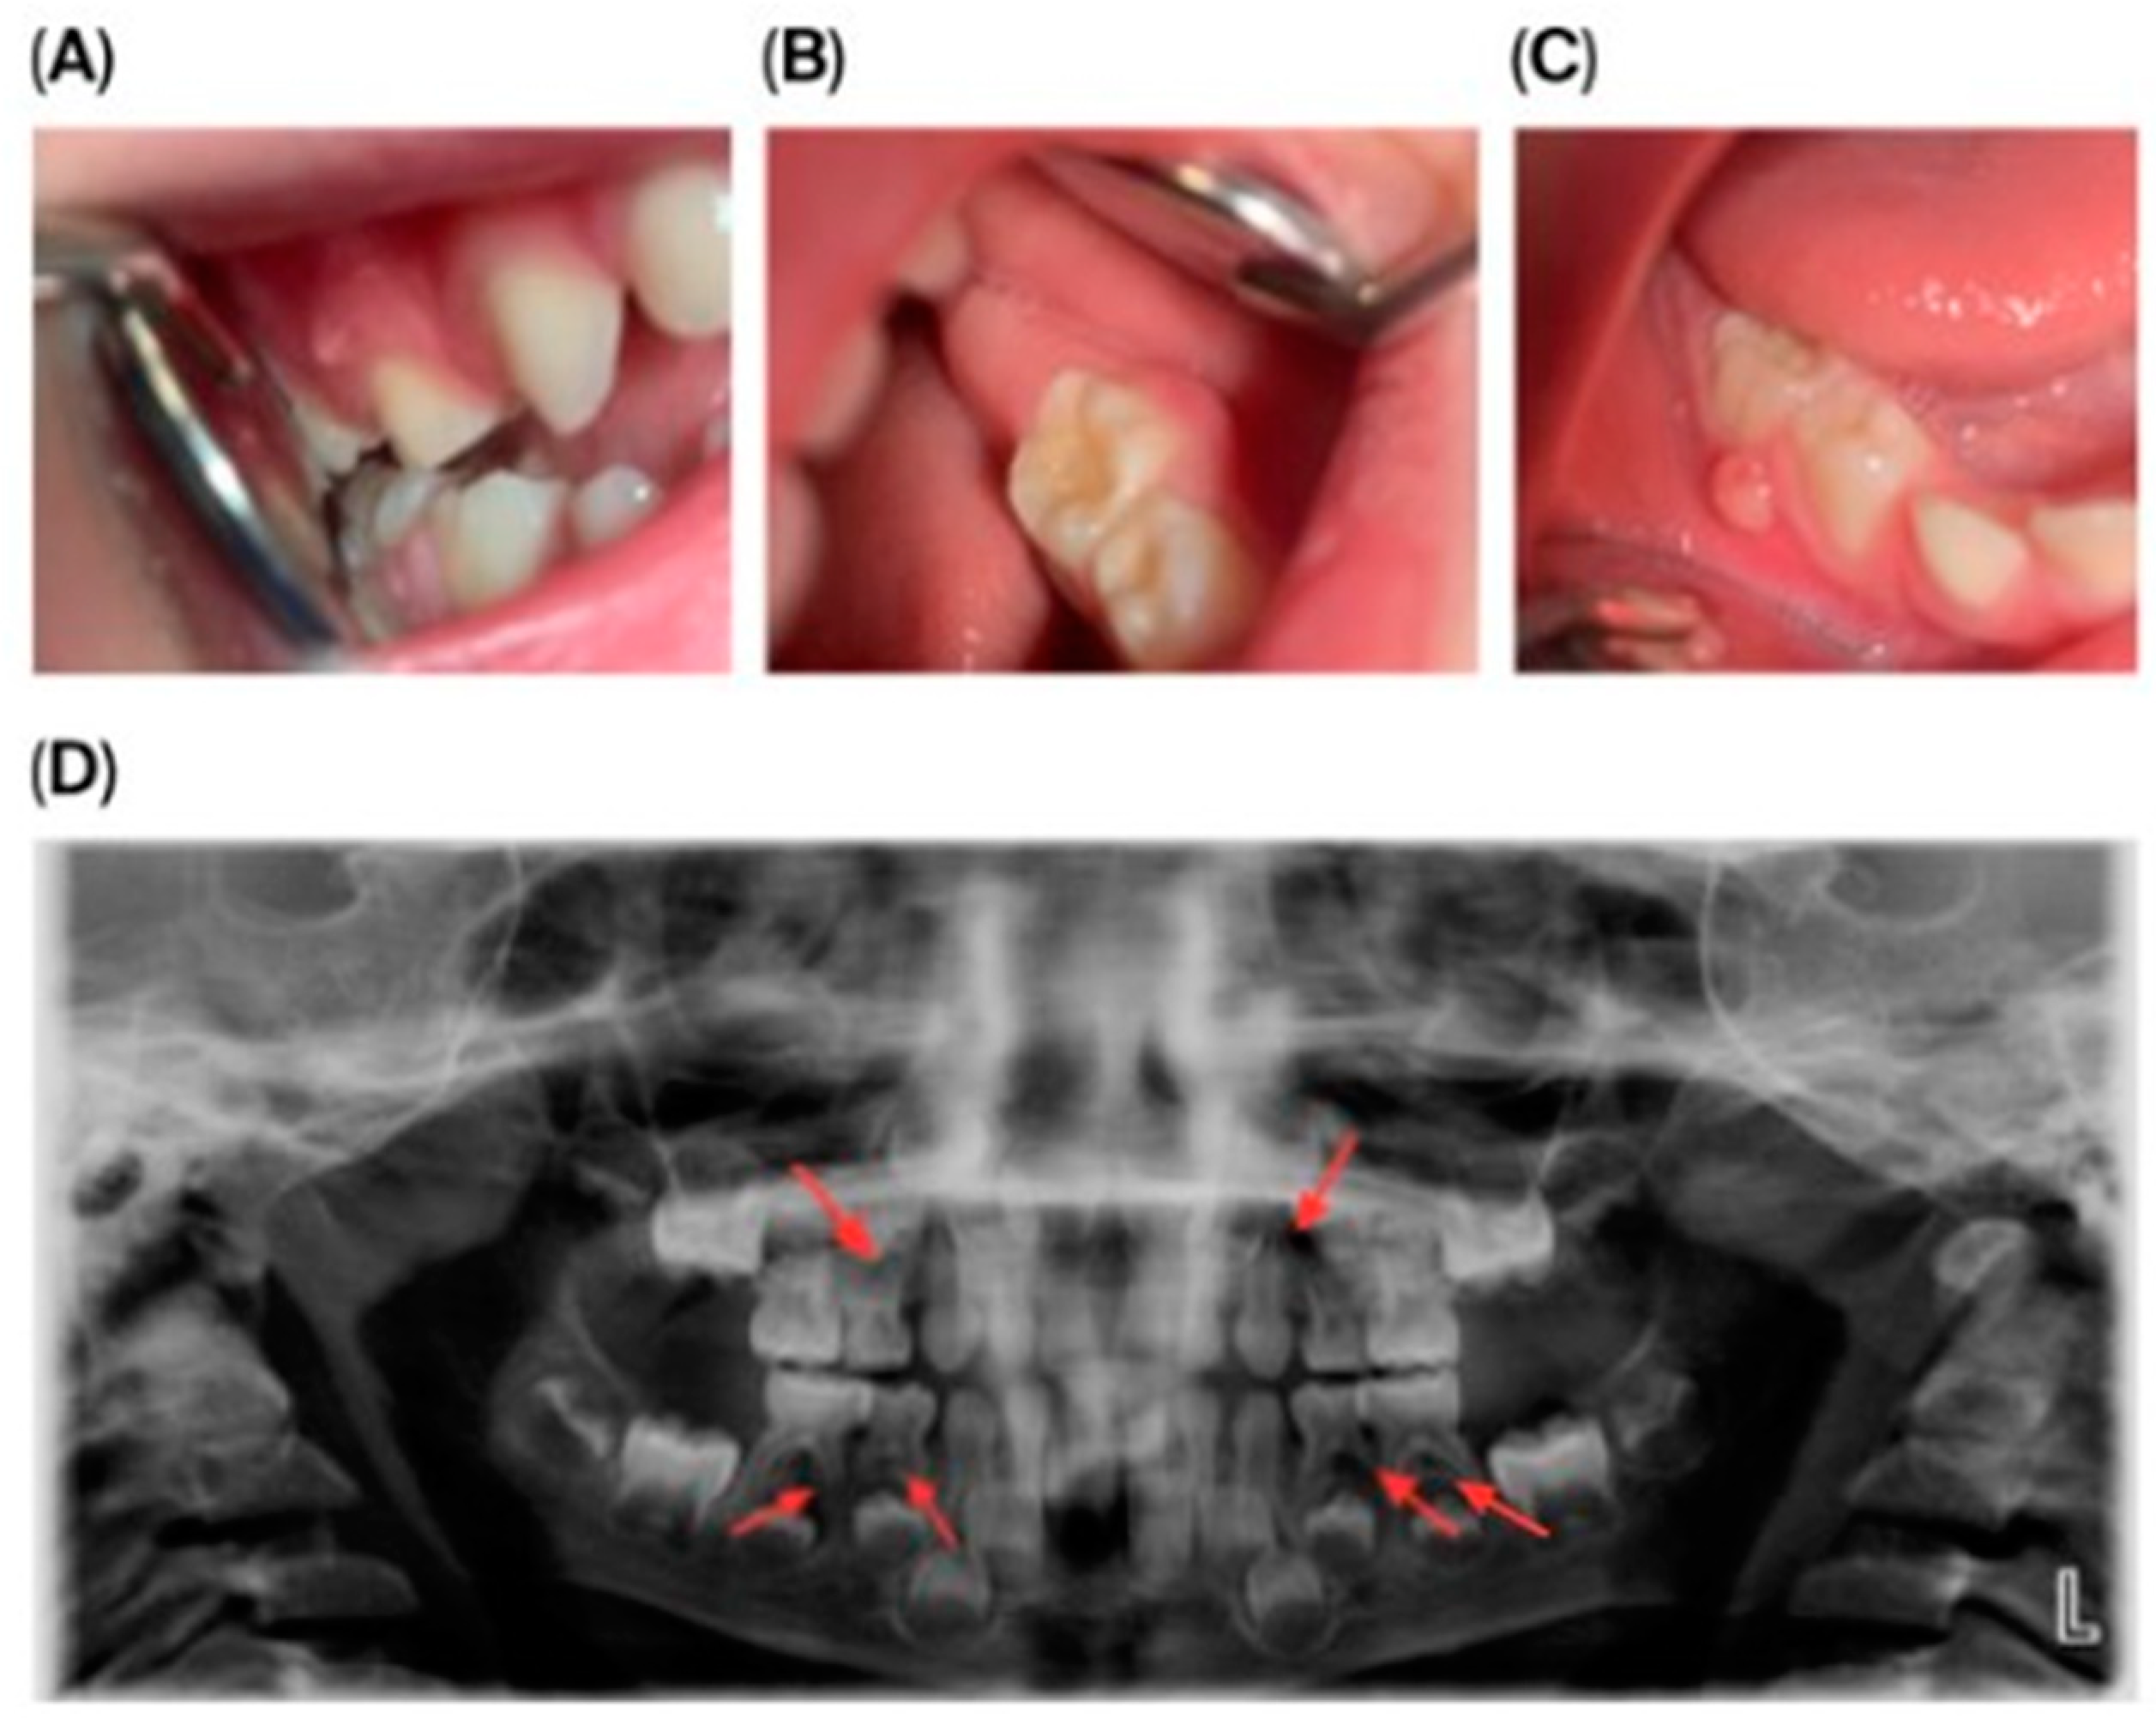

Initial dental management focused on infection control and the preservation of dental function. A formalin–resorcinol endodontic protocol was applied to the affected primary molars, followed by long-term glass–ionomer cement restorations (VOCO GmbH, Cuxhaven, Germany) (Figure 2). Due to the child’s uncooperative behavior, treatment required multiple short appointments with behavioral guidance. The clinical team considered that the behavior could be gradually managed, and in agreement with the parents’ informed preference, treatment was carried out in short, sequential sessions rather than under general anesthesia or sedation.

Figure 2.

Radiographic follow-up of upper left first primary molar showing initial and post-treatment periapical status, and panoramic overview. (A) Pre-treatment periapical radiograph of the upper left first primary molar. (B) Post-treatment periapical radiograph showing healing after formalin–resorcinol endodontic protocol and glass–ionomer cement restoration. (C) Panoramic radiograph (OPG, 2025) demonstrating overall progression of dental treatment and status of other primary molars.

Given the patient’s limited cooperation, the lack of alternative methods capable of effectively controlling the periapical inflammation in this specific pathogenic context, and the need to maintain the primary teeth until their physiological exfoliation, a resorcinol–formalin technique was selected. This approach represented the only practically effective option in a situation characterized by spontaneously developing pulp necroses in clinically intact teeth.